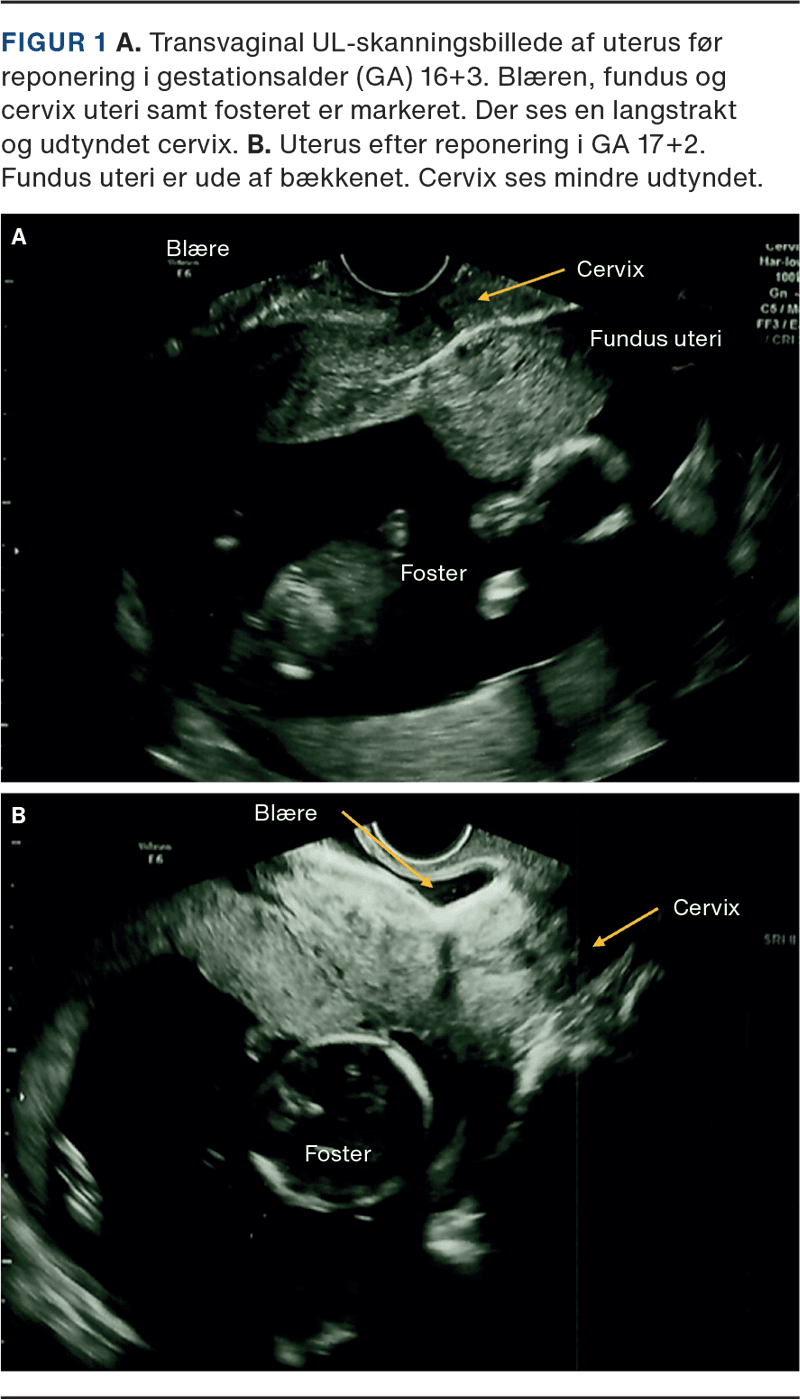

På hospitalet blev der anlagt et permanent kateter à demeure (KAD), og blæren blev tømt for 950 ml klar urin. Ved abdominal palpation var uterus mindre end forventet. Ved transvaginal UL-skannning fandt man en intrauterin graviditet svarende til GA. Fundus uteri var beliggende i fossa Douglasi og med cervix aflang og udtyndet (Figur 1A). Ved den gynækologiske undersøgelse fandtes uterus øm og posteriort placeret. Patienten blev diagnosticeret med inkarcereret uterus, og man forsøgte uden held at manipulere uterus ud af bækkenet. Pga. GA og stor urinretention blev KAD bibeholdt i 48 t., og i et forsøg på at ryste uterus ud af bækkenet blev patienten anbefalet at udføre yogastillingen downward facing dog. Her står man på alle fire med strakte ekstremiteter og med sædet i vejret. Patienten udførte yogaøvelsen a fem minutters varighed. Ved kontrol to dage senere seponeredes KAD, og patienten havde ikke længere urinretention. Ved abdominal palpation var uterus svarende til GA. Ved transvaginal UL-skanning fandt man uterus mere anteflekteret med et levende foster (Figur 1B). Patienten blev anbefalet vandladning hver tredje time. Til gennemskanningen så man en fortsat normal udviklet graviditet.